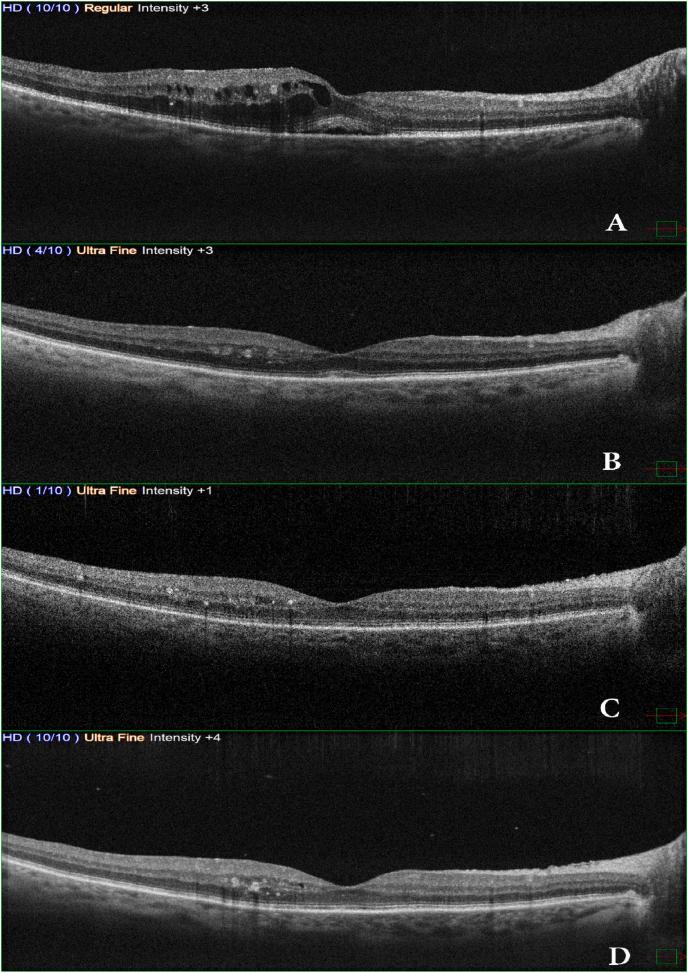

METHODS

This case report is an interventional case of a 52-year-old female presented with a four-week history of reduced vision secondary to Pseudophakic cystoid macular edema (PCME). The patient attended Marashi Eye Clinic Center for a clinical examination and followed up with Optical Coherence Tomography (OCT) at baseline. The patient was treated by one injection of triamcinolone acetonide and followed up within one week, 4 weeks, 8 weeks, 16 weeks, and 24 weeks in the suprachoroidal space (SCS) using a manually made needle with assessing the efficacy and potential ocular complications.

RESULTS

The best-corrected visual acuity (BCVA) had improved significantly from baseline 20/60 to 20/30 at 24 weeks with a complete anatomical resolution of macular edema at 24 weeks from baseline. No ocular complications were noticed during the study period.

本病例报告是一例52岁女性的介入性病例,该患者因人工晶状体眼黄斑囊样水肿(PCME)出现视力下降四周。患者前往马拉希眼科诊所中心进行临床检查,并在基线时接受光学相干断层扫描(OCT)检查。患者接受了一次曲安奈德注射治疗,并在一周、4周、8周、16周和24周时使用自制针头在脉络膜上腔(SCS)进行随访,评估疗效和潜在的眼部并发症。

结果

最佳矫正视力(BCVA)从基线时的20/60显著提高到24周时的20/30,黄斑水肿在24周时从基线开始完全解剖学消退。在研究期间未发现眼部并发症。